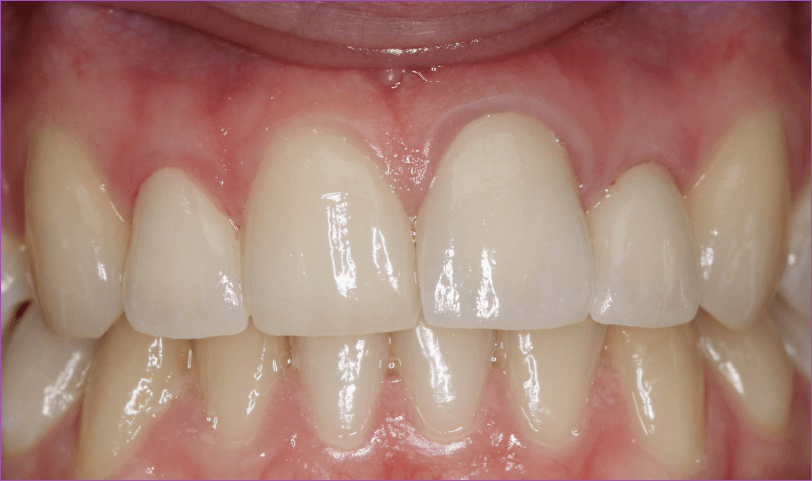

4. Próba

Többnyire egy bő hét alatt elkészül a korona vagy a híd, bár ez több időt is igénybe vehet. Mikor ez az idő letelt, jöhet a próba. Ha a korona vagy a híd tökéletesen illeszkedik, és a színe is megfelel a meglévő fogakénak, a fogtechnikusnak még egy-két napra szüksége lehet a véglegesítésre. Ha ez megvan, a koronát vagy hidat a helyére rögzítjük.